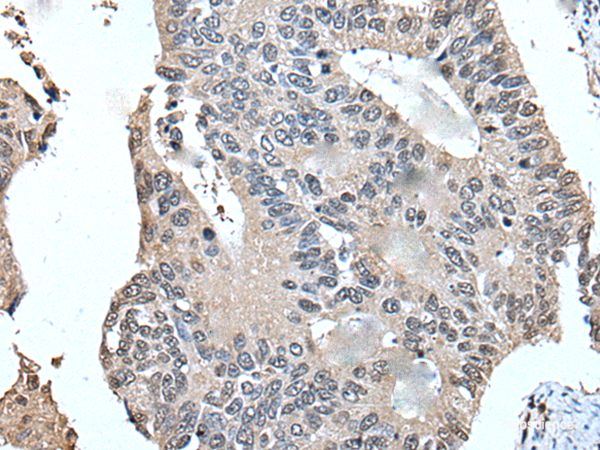

UFM1 is a ubiquitin-like protein that is conjugated to target proteins by E1-like activating enzyme UBA5 (UBE1DC1, MIM 610552) and E2-like conjugating enzyme UFC1 (MIM 610554) in a manner analogous to ubiquitylation (see UBE2M, MIM 603173) (Komatsu et al., 2004 [PubMed 15071506]). Protein function: Ubiquitin-like modifier which can be covalently attached via an isopeptide bond to substrate proteins as a monomer or a lysine- linked polymer (PubMed:15071506, PubMed:20018847, PubMed:29868776). The so-called ufmylation, requires the UFM1-activating E1 enzyme UBA5, the UFM1-conjugating E2 enzyme UFC1, and the UFM1-ligase E3 enzyme UFL1 (PubMed:15071506, PubMed:20018847, PubMed:29868776). This post- translational modification on lysine residues of proteins may play a crucial role in a number of cellular processes (PubMed:15071506, PubMed:20018847). TRIP4 ufmylation may for instance play a role in nuclear receptors-mediated transcription (PubMed:25219498). Other substrates may include DDRGK1 with which it may play a role in the cellular response to endoplasmic reticulum stress (Probable). [The UniProt Consortium]